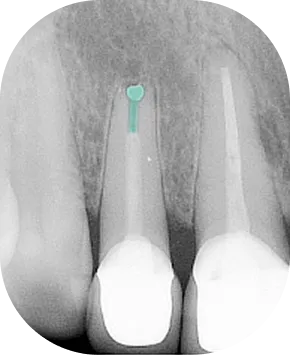

Resekce kořenového hrotu zubu a retrográdní zaplnění kořenového kanálku

Tyto zákroky se provádějí, když nelze infekci v kořeni zubu odstranit nechirurgickým (orthográdním) ošetřením. V čelistní kosti pak často vzniká zánětlivé či cystické ložisko, které je nutné chirurgicky odstranit spolu s hrotem kořene – hlavním zdrojem infekce. Kořen se následně retrográdně opracuje a vyplní materiálem MTA. Takto ošetřený zub obvykle zůstává dlouhodobě zachován a funkční.